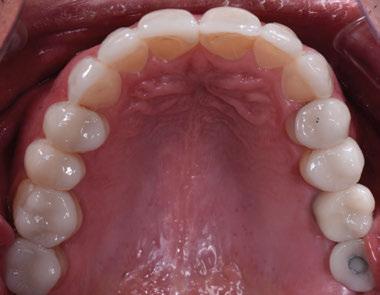

dentarias, cumpliendo parámetros biológicos, terapéuticos, mecánicos y estéticos. Después se realizó un modelado digital retrospectivo (Figuras 7-11) para generar modelos impresos 3D para realizar el mock up funcional, estético y como guía para las preparaciones (Figuras 12-15). Con ello, se efectuaron las preparaciones dentarias y los registros intermaxilares y, posteriormente, se digitalizaron ambos maxilares (Figuras 16-21)

Finalmente, las restauraciones se cementaron adhesivamente (Figuras 31-35). En las piezas 16 y 17 se realizaron restauraciones cementoatornilladas como última fase de tratamiento. Se recomendó al paciente una férula de protección superior la cual fue elaborada mediante un flujo de trabajo digital (Figura 36)

Figura 33. Vista oclusal superior. Figura 34. Vista oclusal maxilar Inferior. Figura 31. Restauraciones cementadas, vista anterior superior. Figura 32. Restauraciones cementadas, vista anterior inferior. Figura 35. Vista en oclusión del caso terminado.

Figura 36. Férula de protección.